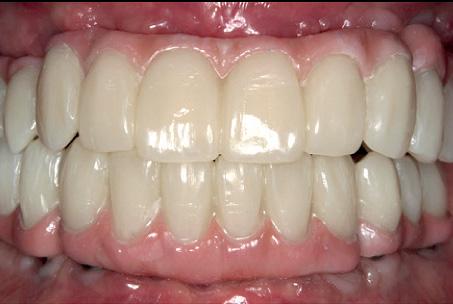

To achieve good primary closure, it was decided to modify the procedure and trim the roots up to the furcation to ensure a sound collar of alveolar bone and advance the buccal flap. This modification helped significantly during primary closure of the socket. LL8 tooth was removed completely as the roots became loose as well as UR8 and LU8. The post-operative phase was uneventful, and she recovered well (Fig 4).

Implant prosthetics and dental prosthetics differ considerably, with the absence of periodontal ligament in the implant/ prosthesis complex. This situation causes mechanical problems to the implants, especially to the implant prosthetic material, due the lack of stress absorption resulting from the normal impact during chewing (1) (2). Among the problems we face in daily practice is the unscrewing and fracturing of veneering material of the implant crown and fracturing of implant/ abutment components.

It is very important to consider that resin based blocks give us the missing part from ceramic materials to solve the problem of anterior exposure. It is also necessary to consider the importance of reliable bonding/union between the resin block and the abutment component of the

implant, because the right transmission of occlusal load depends on the reliability of this bonding interface. One of the biggest advantages of BRILLIANT Crios blocks is the combination with ONE COAT 7 UNIVERSAL, the best bonding system for the resin based blocks according to the scientific literature (3) (4) and also tested in my own practice over the last five years of use.

During daily practice, it is very common to face situations where the implant has to be placed lingually due to normal resorption (Fig. 1) of the buccal plate after the extraction. But, at the same time, it is not necessary to perform bone grafting procedures. The result of this scenario is to increase the stress on the implant-bone complex when we use rigid materials like conventional ceramics (Fig. 2).

For this daily practice situation, the combination of rigid and resilient materials against the antagonist, allows the stress to the implant-bone complex to be reduced (Fig. 3,4).

Another common situation is a full mouth restoration over implant. It is well known that the big issue is chipping and delimitation of the ceramics, due to the high forces applied in the patient with dental implants.

In regards to this problem, the combination of rigid materials to support the connectors and resilient materials to absorb the shock and, at the same time, allow easy fixation, make the use of resin based blocks the logical choice for this kind of restoration. (Fig. 6,7 and 8)

Fig. 17: BRILLIANT Crios restorations used for removable telescopic implant prosthesis.

Fig. 18: Final case in the mouth of the patient. Wearing a complete denture on top and tele-scopic BRILLIANT Crios on the